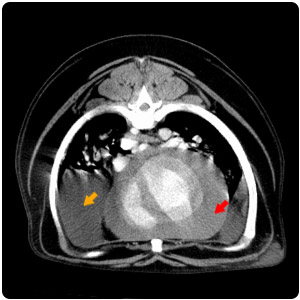

脊椎旁腫塊(黃)、脾腫塊(紅) |